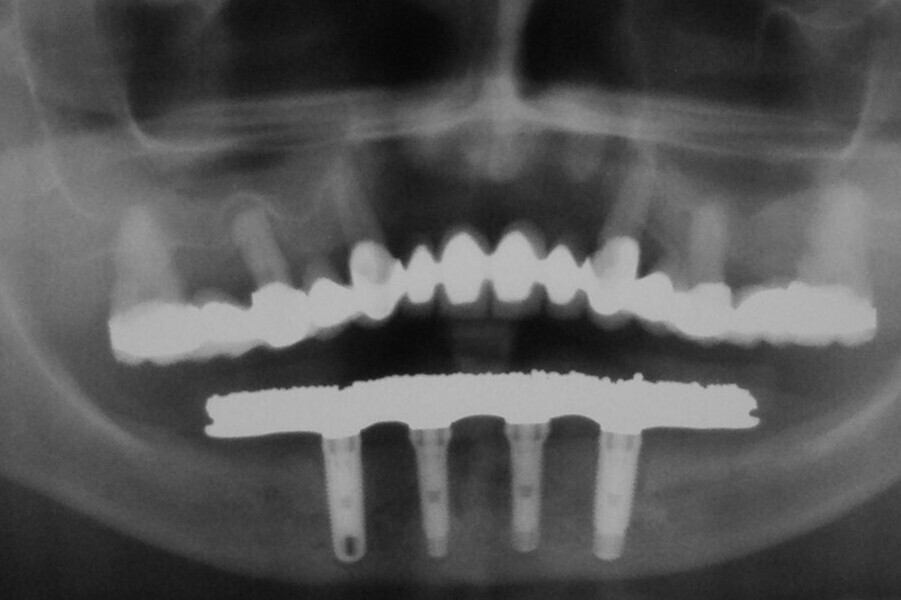

Fig. 7. Rx Pre-operatoria, Prótesis híbrida inmediata con 10 años de evolución y Rx Control a los 10 años.

Fig. 8. Rx Pre-operatoria, Prótesis híbrida inmediata con 10 años de evolución y Rx Control a los 10 años.

Fig. 9. Rx Pre-operatoria, Prótesis híbrida inmediata con 10 años de evolución y Rx Control a los 10 años.